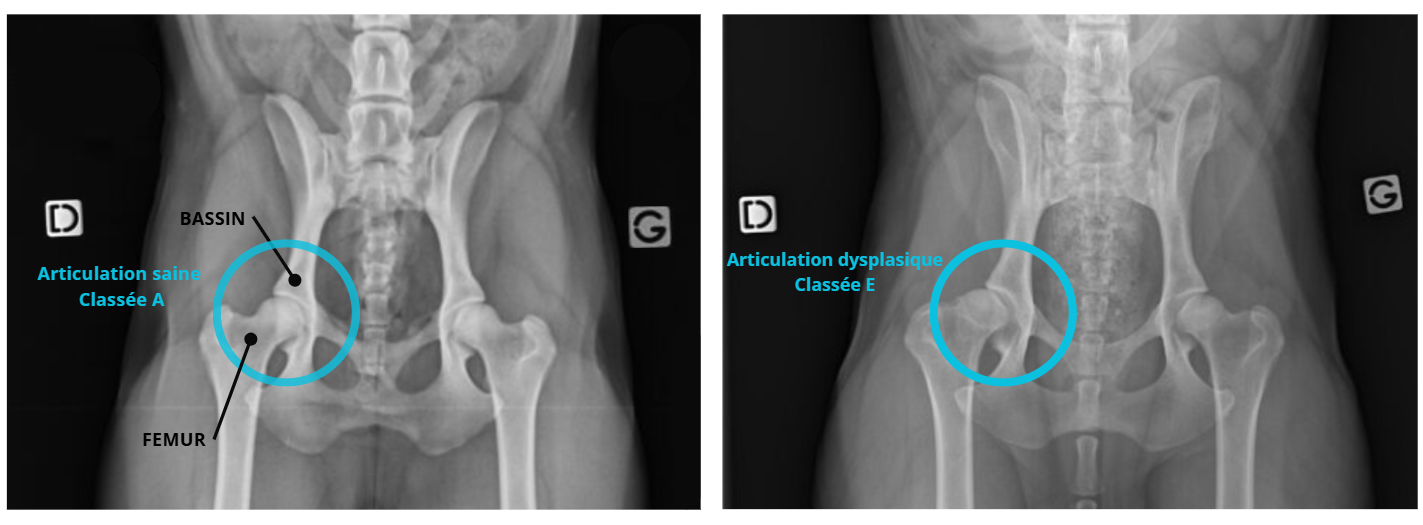

La dysplasie canine des hanches ou des coudes est classée selon un système de notation établi après une radiographie officielle. Pour les hanches, on utilise une échelle allant de A à E :

A correspond à des hanches normales,

B indique une conformation presque normale,

C à E traduisent des degrés croissants de dysplasie, de légère à sévère.

Ces notations sont essentielles pour le suivi vétérinaire. Les éleveurs doivent sélectionner les parents en fonction. Elles permettent aussi l’adaptation du programme de soins ou de prévention ostéopathique. Il faut toujours demander les preuves des tests des parents lorsque vous prenez un chiot, cela témoigne aussi de la qualité de votre élevage !